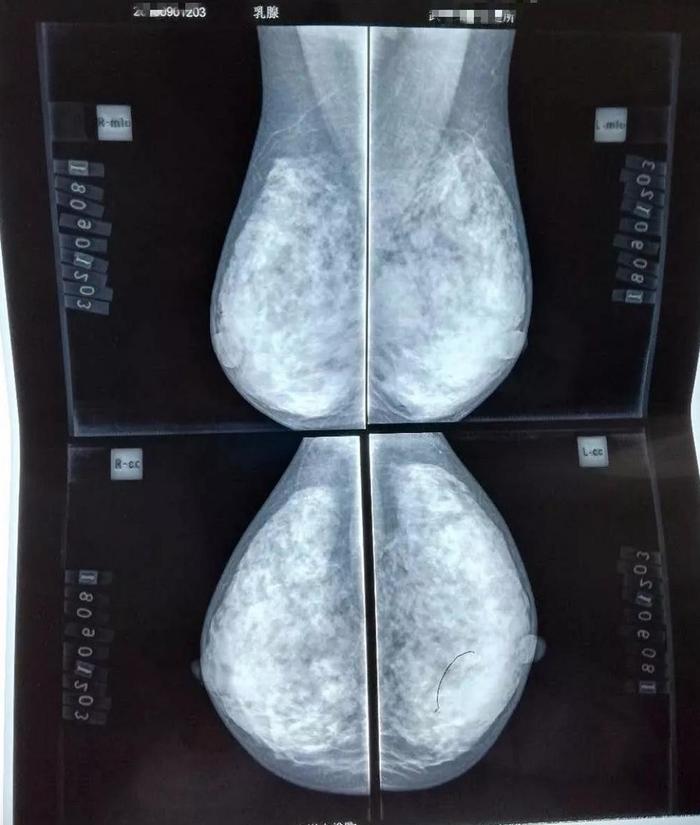

张某,40岁,钼靶检查发现左乳钙化灶1月入院;查体:双侧乳腺对称,乳头无

乳腺钼靶片分析